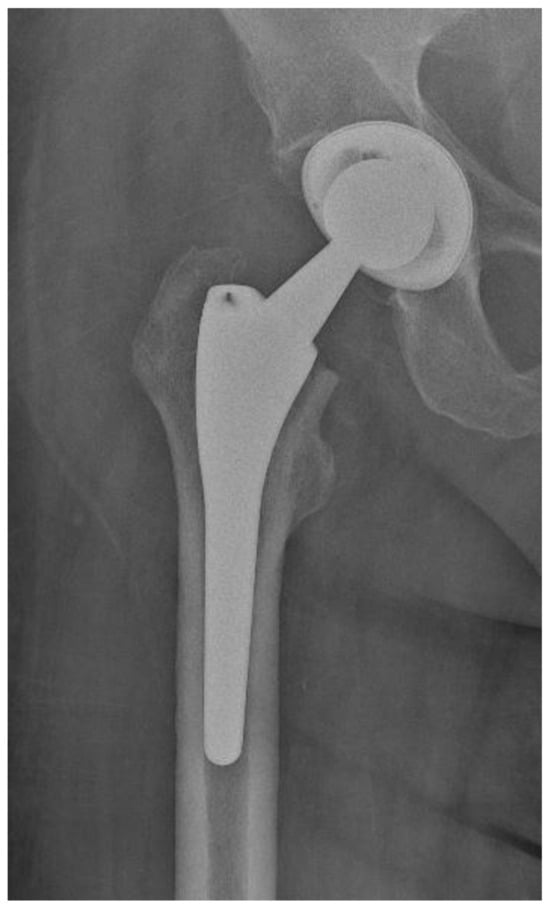

Of the 84 patients enrolled in this study, 44 patients (52.4%) received a THA with a straight stem (group A) (Figure 1 and Figure 2) and 40 patients (47.6%) received a THA with an anatomical stem (group B) (Figure 3 and Figure 4).

Figure 2.

Axial X-rays view of a total hip arthroplasty with straight stem (group A).